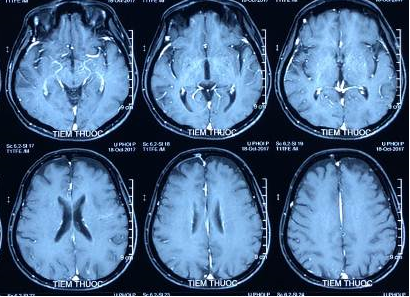

- Chụp cộng hưởng từ sọ não: không có tổn thương bất thường.

Hình 2: Hình ảnh chụp cộng hưởng từ sọ não có tiêm thuốc đối quang từ